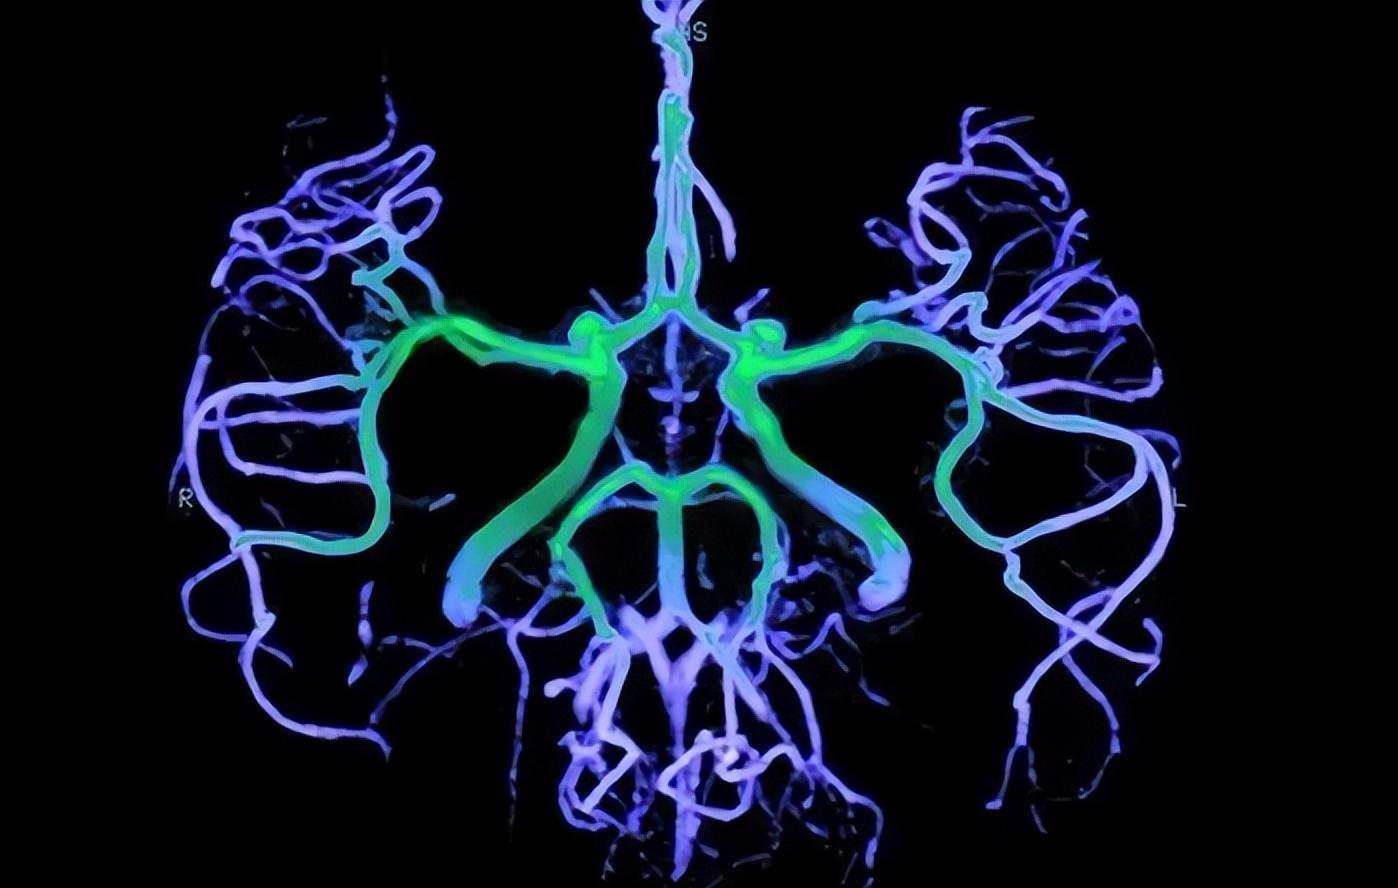

冠脉造影是一项诊断冠脉疾病非常有效的技术,它利用血管造影仪器,然后通过特定型号的导管,将其经皮穿刺进入下肢的股动脉,沿着患者的主动脉进入升主动脉,然后找到左右冠脉插口,注射造影剂,这样的话冠脉造影就能很好的成像了。

冠脉造影的出现,主要就是为了看清楚冠状动脉的病变,因此帮助诊断应该是冠脉造影技术出现的主要原因。那么它的适应症有哪些?